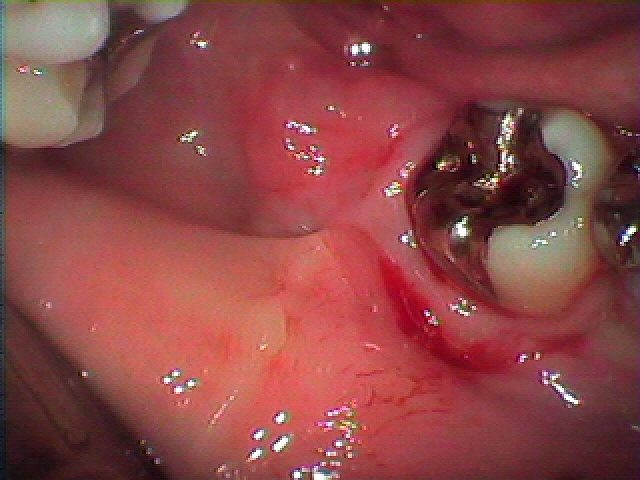

親不知の完全水平埋伏歯抜歯。| |広島市安佐南区の歯科医院 親不知の完全水平埋伏歯抜歯。 トップ お知らせ・ブログ 親不知の完全水平埋伏歯抜歯。 親不知の完全水平埋伏歯抜歯。 Web診療予約 初めての方へ 選ばれ続ける理由 院内設備について 歯が痛いしみる一般歯科 歯がぐらぐらする歯周病 健康な歯を保ちたい予防歯科 子供の虫歯予防をしたい小児歯科 銀歯をセラミックに審美歯科 白い歯を目指しませんか?ホワイトニング 矯正専門医がいるので安心矯正歯科 抜けた歯を補いたいインプラント・入れ歯 医院案内 スタッフ紹介 メリィハウス歯科クリニックオフィシャルホームページ ラベンダー歯科クリニックオフィシャルホームページ お知らせ・ブログ ホーム 診療科目 一般歯科 歯周病治療 予防治療 小児歯科 審美治療 ホワイトニング 矯正歯科 入れ歯・インプラント マウスピース矯正 初めての方へ 院長・スタッフ 設備紹介 医院案内・アクセス メニューを閉じる